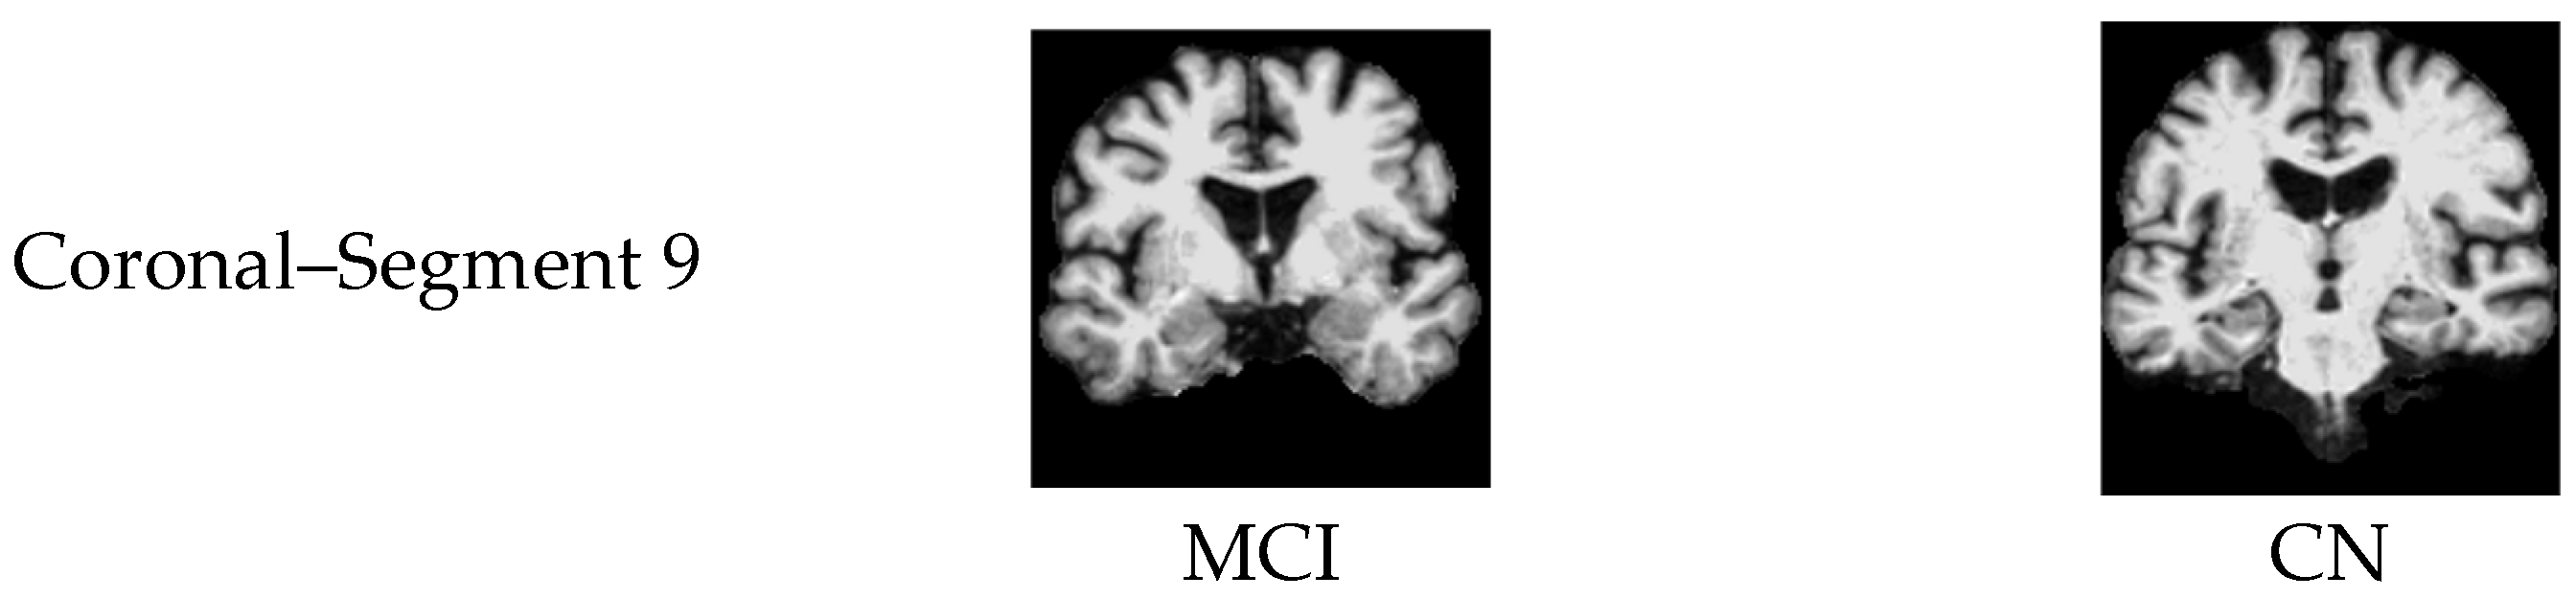

3.3. Automated 2D Slice Selection